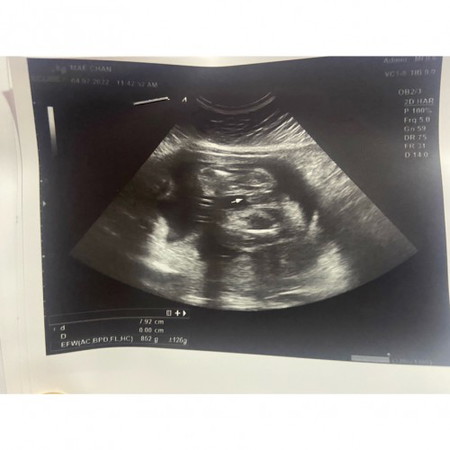

ซาวด์วันนี้หมอบอกเป็นผู้ชาย เป็นผู้ชายจริงๆใช่มั้ยค่ะ แต่เพื่อนบางคนบอกให้รอดูตอนคลอด เลยรู้สึกไม่ค่อยมั่นใจค่ะ

ตรงลูกศร มีชี้ๆ ยื่นออกมาก็ผู้ชายค่ะ 😁